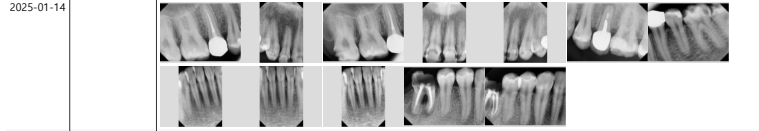

You can also check on the panoramic image

that the treatment was carried out successfully.

Currently, the implant is in a state where only the fixture,

which is the artificial root part,

has been placed,

and we plan to complete the prosthetic process

by later placing the crown (prosthesis).